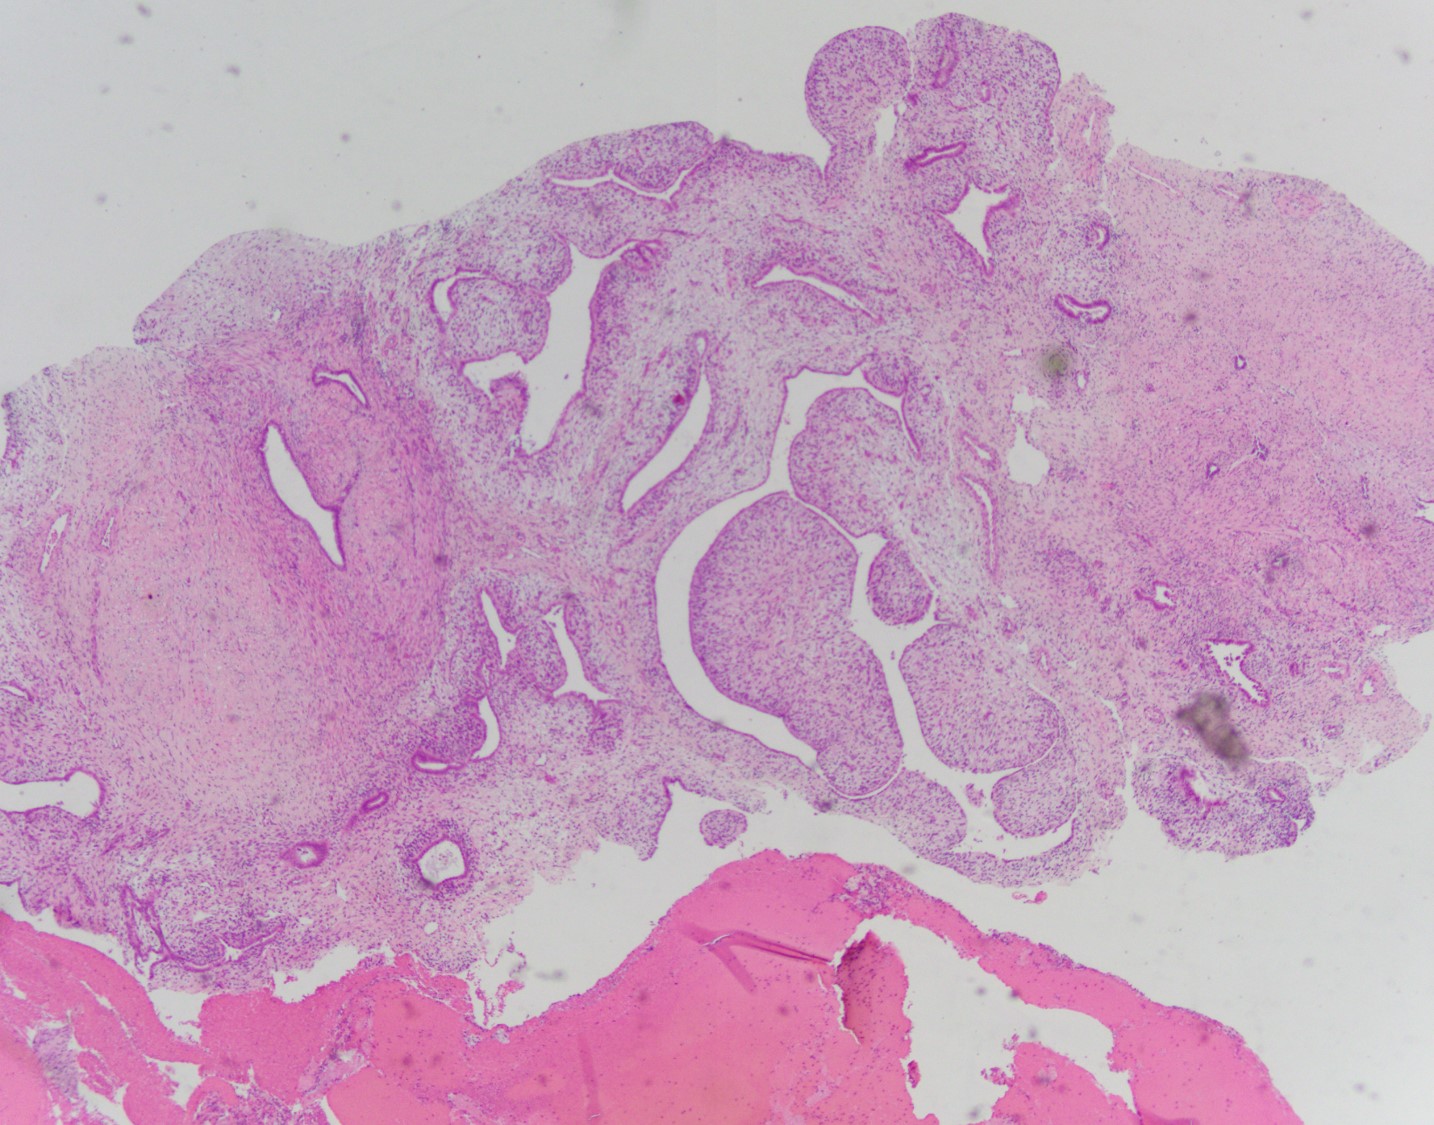

Histologically, MA usually have a phyllodes-type pattern with dilated glands lined by benign endometrial or ciliated epithelium surrounded by a distinct cuff of neoplastic stroma. This stroma is normally hypercellularand can have subtle atypical features. These tumors are often positive for CD10, ER, and PR, however there have been a subset of cases that are negative for CD10.

There are two components comprising this specimen, which are focally intimately associated with one another. The first component consists of endometrial glands and stroma surrounded by smooth muscle bundles, which in the proper clinical setting could represent a benign adenomyomatous polyp. The second component consists of a biphasic process of benign glands and stroma with a phyllodes-like architecture. The stroma surrounding the glands shows periglandular "cuffing" with very low-grade atypia. There is increased mitotic activity (greater than 2 mitoses/10 HPF) in the areas with the phyllodes-like architecture. Immunohistochemical staining showed two distinct staining patterns in the two components. The adenomyomatous polyp component showed CD10 highlighting endometrial stroma in the adenomyomatous areas with surrounding smooth muscle bundles positive for caldesmon and desmin while the stroma in the phyllodes-like area was positive for desmin and caldesmon but was negative for CD10. The patient was treated with a hysterectomy, where there was minimal focal residual disease identified.